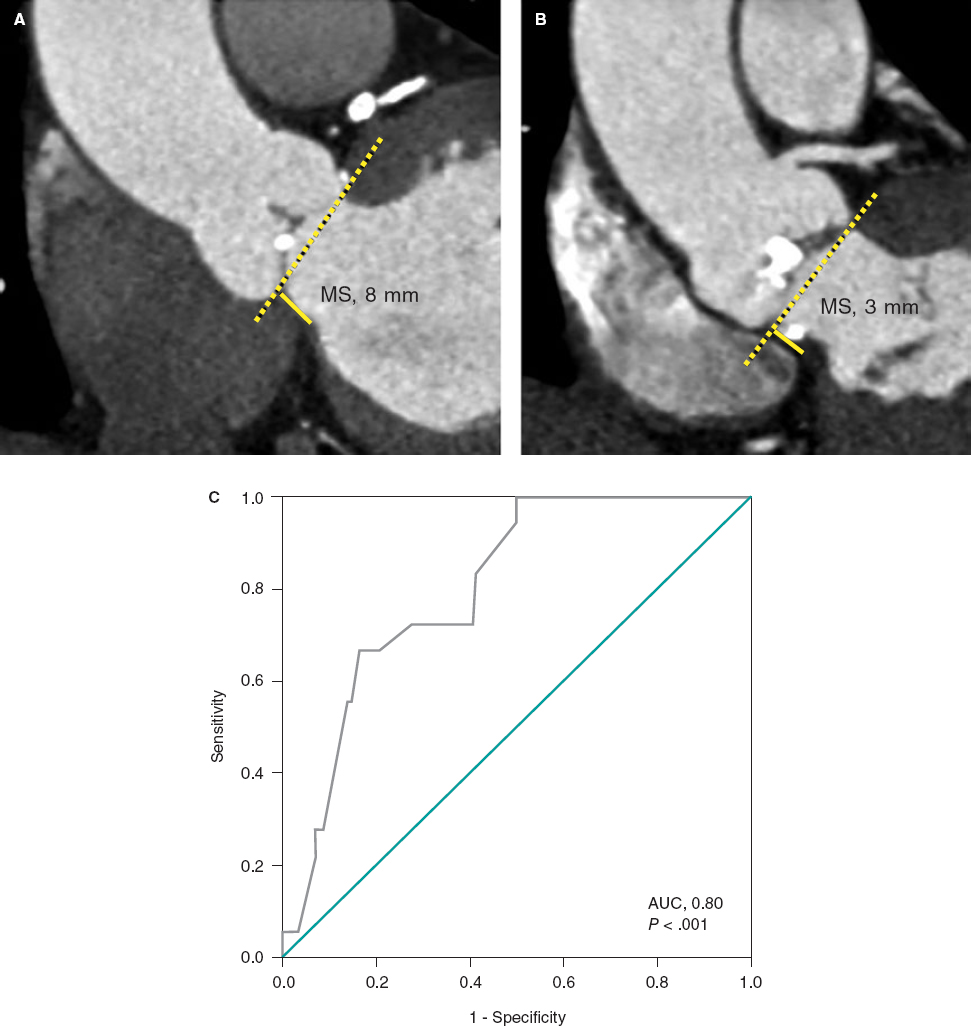

The angiographic results were good (figure 5A) and the intravascular ultrasound examination conducted showed the double layer of stents at ostium level with good stent apposition and expansion (figure 5B1) and the stent deployed protruding into the aorta showed wide overexpansion (figure 5B2).

Figure 5. A: final angiographic result. B1: intracoronary ultrasound image showing the double layer of stents at ostium level with good stent apposition and expansion. B2: intracoronary ultrasound image showing the stent implanted in the first place, protruding into the aorta, and showing wide overexpansion.